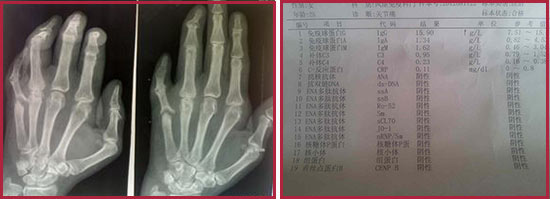

類(lèi)風(fēng)濕性關(guān)節(jié)炎病情很多,病情復(fù)雜,容易和多種關(guān)節(jié)疾病混淆,因此在治療前一定要對(duì)病情病因進(jìn)行詳細(xì)的檢查。臨床上檢查類(lèi)風(fēng)濕性關(guān)節(jié)炎的方法很多,常規(guī)的檢查方法有:類(lèi)風(fēng)濕因子檢查、血沉、c反應(yīng)蛋白檢查、X線檢查等,單獨(dú)采用這類(lèi)常規(guī)檢查方法存在一定的漏診和誤診風(fēng)險(xiǎn),要想有效掌握類(lèi)風(fēng)濕病情,必須要有更科學(xué)專業(yè)的檢查方法。那么常規(guī)檢查有哪些?更專業(yè)的檢查又有哪些呢?

(圖:類(lèi)風(fēng)濕性關(guān)節(jié)炎常規(guī)檢查和X線檢查結(jié)果)

類(lèi)風(fēng)濕性關(guān)節(jié)炎的常規(guī)檢查方法有哪些?

、X光片檢查:早期X線可以看到受累關(guān)節(jié)周?chē)浗M織腫脹,晚期為關(guān)節(jié)半脫位、畸形及強(qiáng)直。

第二、類(lèi)風(fēng)濕因子:對(duì)于診斷具有比較重要的參考價(jià)值。但是類(lèi)風(fēng)濕因子陰性不能排除本病的可能,須結(jié)合臨床。

第三、C反應(yīng)蛋白及血沉:C反應(yīng)蛋白與病情活動(dòng)指數(shù)、晨僵時(shí)間、握力、關(guān)節(jié)疼痛及腫脹程度、血沉和血紅蛋白水平密切相關(guān),病情緩解時(shí)C反應(yīng)蛋白下降,反之則上升。C反應(yīng)蛋白水平持續(xù)不降多提示病變的進(jìn)展,病情加重則血沉加快,病情緩解時(shí)可恢復(fù)至正常,但約有5% 的類(lèi)風(fēng)濕關(guān)節(jié)炎患者在病情活動(dòng)時(shí)血沉并不增快。

第四、血常規(guī):類(lèi)風(fēng)濕性關(guān)節(jié)炎患者可伴有貧血,白細(xì)胞數(shù)大多正常,在活動(dòng)期可略有增高。貧血和血小板增多癥與疾病的活動(dòng)相關(guān)。多數(shù)病例的紅細(xì)胞沉降率在活動(dòng)性病變中常增高,可為疾病活動(dòng)的指標(biāo)。血清鐵、鐵結(jié)合蛋白的水平常減低。

【臨床指導(dǎo)】類(lèi)風(fēng)濕性關(guān)節(jié)炎通過(guò)以上四種常規(guī)檢查方法能初步診斷是否患病,病情嚴(yán)重程度等,這四項(xiàng)常規(guī)檢查也是臨床上使用比較廣的檢查方法。但是這種檢查方法是類(lèi)風(fēng)濕的基礎(chǔ)檢查方法,不夠詳細(xì),容易將類(lèi)風(fēng)濕性關(guān)節(jié)炎與其它類(lèi)似骨關(guān)節(jié)疾病混淆,出現(xiàn)誤診的情況。為了避免常規(guī)檢查容易出現(xiàn)的誤診漏診弊端,我院采用更專業(yè)的檢查技術(shù)-分層診斷,詳細(xì)診斷病情。